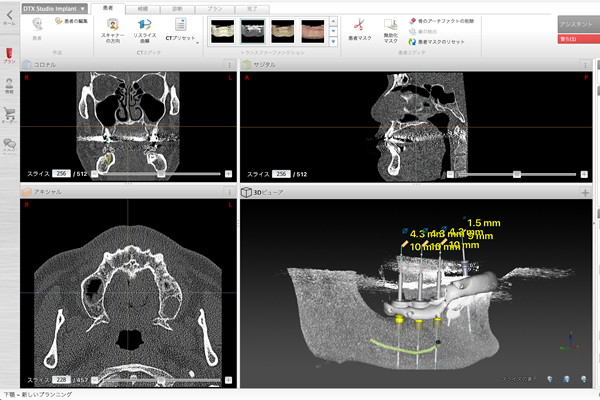

当院では、CTデータを活用したインプラント治療のためのシミュレーションソフトウェア「DTX Studio™ Implant(DTXスタジオ)」を採用しています。

この先進的なシステムを用いることで、インプラントの埋入から、最終的な歯の設置までの詳細な治療計画を立てることが可能です。

これにより、予測性と安全性が大幅に向上し、より精密で信頼性の高いインプラント治療を提供しています。

正確なインプラント治療を行うには、サージカルガイドシステムを使用し、正しい埋め込み位置に正しくインプラントを埋めることが重要です。

そのため「DTXスタジオ」と呼ばれるシステムを使用して、人工歯根を埋め込む場所の「ガイド(目印)」を作成し、埋め込みを行います。

最も世界で治療実績のあるノーベルバイオケア社の「DTXスタジオ」を導入しておりますので、

一般的なサージカルガイドよりもズレないため、より正しい位置に埋め込みを行うことが可能です。